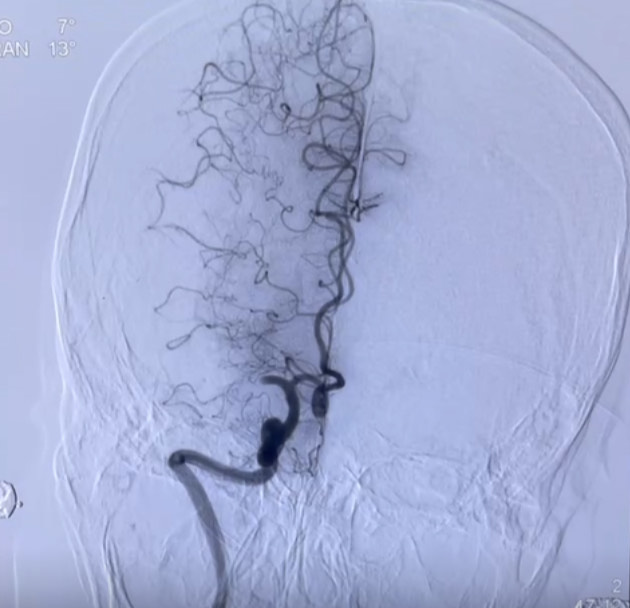

Điển hình là trường hợp bệnh nhân nữ L.T.N 69 tuổi, tiền sử khỏe mạnh, vào viện khoa Cấp cứu ngày 11/4/2025 vì lý do ý thức chậm, nói khó, méo miệng, liệt vận động hoàn toàn nửa người trái giờ thứ 3. Ngay sau khi tiếp nhận thông tin, bác sĩ trực và kíp can thiệp khoa Đột quỵ đã có mặt tại khoa Cấp cứu tiến hành thăm khám đánh giá bệnh nhân, kết hợp hình ảnh chụp CLVT sọ não và điện tim đồ bệnh nhân được chẩn đoán: Nhồi máu não cấp giờ thứ 4 do tắc động mạch não giữa bên phải/ Rung nhĩ. Xác định đây là trường hợp huyết khối tắc mạch lớn cần phải phối hợp các phương pháp điều trị, bác sĩ trực đã giải thích gia đình và tiến hành sử dụng thuốc tiêu sợi huyết đường tĩnh mạch đồng thời đẩy thẳng bệnh nhân lên phòng can thiệp mạch cấp cứu. Hình ảnh chụp mạch não số hóa xóa nền DSA cho thấy bệnh nhân bị tắc hoàn toàn động mạch não giữa bên phải. Kíp can thiệp đã triển khai phương pháp tái thông mạch não bằng dụng cụ cơ học. Kết quả, sau 02 lần hút đã tái thông hoàn toàn động mạch não giữa bên phải đạt mức TICI 3. Hiện tại ngày thứ 10 sau can thiệp, tình trạng bệnh nhân ổn định: Ý thức tỉnh G15đ, nói rõ, liệt nhẹ VII TW bên trái, liệt nửa người trái cải thiện tốt.

Hình ảnh trước và sau can thiệp tái thông mạch não bằng dụng cụ cơ học